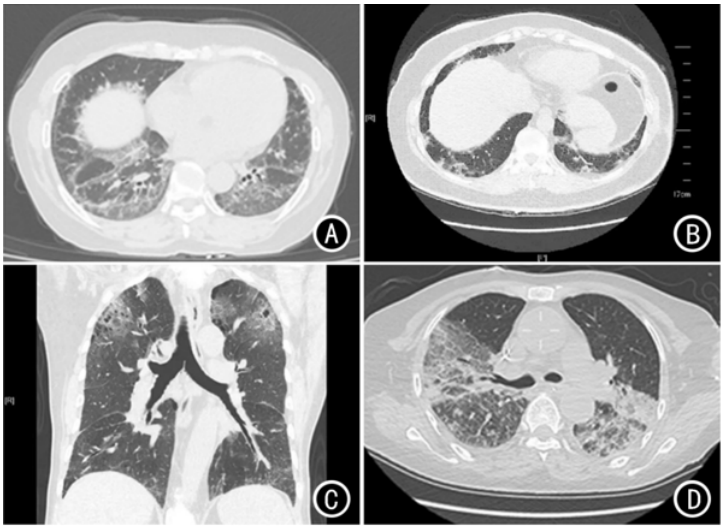

抗血管生成药物可作用于肿瘤微环境,使现有肿瘤血管退化,抑制肿瘤新生血管生成。与其他非小细胞肺癌(NSCLC)系统治疗药物(包括化疗、小分子靶向治疗、免疫治疗)联合使用可发挥更好的抗肿瘤作用。NSCLC的抗血管生成治疗主要包括三大类:①靶向血管内皮细胞生长因子(VEGF)及其受体(VEGFR)的大分子单克隆抗体,例如:贝伐珠单抗、雷莫芦单抗;②靶点VEGFR的多靶点小分子TKI,除了VEGF/VEGFR以外,血小板源性生长因子/受体(PDGF/PDGFR)、成纤维细胞生长因子/受体(FGF/FGFR)及c-Kit等均是这类药物的作用靶点。③重组人血管内皮抑制素。抗血管生成药物3级及以上不良事件包括高血压、蛋白尿、出血和血栓栓塞事件等。第一代EGFR-TKIs包括吉非替尼、埃克替尼和厄洛替尼;第二代EGFR-TKIs包括阿法替尼和达可替尼;第三代EGFR-TKIs包括奥希替尼、阿美替尼、伏美替尼和贝福替尼、瑞齐替尼、利厄替尼、奥瑞替尼。国内指南也推荐,对具有EGFR基因经典突变的Ⅳ期NSCLC患者一线治疗推荐的药物优先选择第三代EGFR-TKIs。抗肿瘤药物相关ILD的发病机制尚未完全明确,目前认为可能的机制主要包括直接细胞不良反应作用和免疫介导的损伤。细胞毒性药物可以直接损伤Ⅰ型肺泡上皮细胞、毛细血管内皮细胞或气道上皮细胞;药物可作为半抗原或模仿宿主自身抗原来激活免疫细胞,从而引起一系列免疫反应。这两种机制可能受到多种宿主和环境因素的影响,包括年龄、肺部基础疾病、药物代谢或免疫相关基因的遗传易感性等,最终综合参与DILD的发病过程。不同类型抗肿瘤药物相关ILD的疾病进程差异较大,可在用药后短时间内出现,如数日到数周,也可缓慢发生,如用药后数月。抗肿瘤药物相关ILD缺乏特异性的临床表现,轻症患者可无明显临床症状(一般通过影像学检査发现),随着病情进展,可能出现干咳、逐渐加重的劳力性呼吸困难,有些患者可出现乏力、发热、皮疹等全身症状。抗肿瘤药物相关ILD亦缺乏特异性体征,可能的体征包括呼吸频率增快、口唇发绀等。肺部听诊通常正常,部分患者可闻及湿啰音或Velcro啰音等。对既往有肺部基础疾病的患者,在使用抗肿瘤药物过程中,若出现原有呼吸系统症状/体征加重,需排查抗肿瘤药物相关ILD。抗肿瘤药物相关ILD的影像学和病理学检查均无特异性,主要为间质性病变表现,具体见图5和表2。DILD的其他实验室检查包括血液学检查、血气分析、肺功能检查(表3)。如果患者的实验室检查和影像学表现不能明确特定的肺损伤类型,或者根据鉴别诊断不同,需要给予明显不同的治疗策略(如DILD与肺部感染或恶性肿瘤进展),可能需要进行肺活检。对于高度怀疑肿瘤进展的患者,病理活检是非常重要的诊断依据。

图5 药物引起的间质性肺病胸部高分辨率CT表现

注:A:非特异性间质性肺炎样改变;B:机化性肺炎样改变;C:过敏性肺炎样改变;D:弥漫性肺泡损伤样改变。